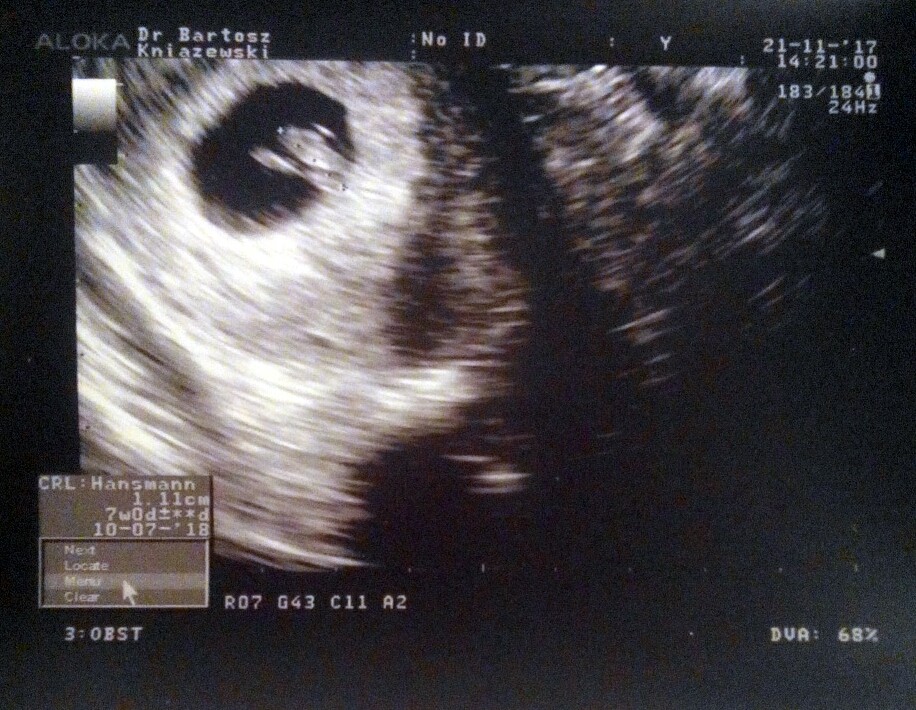

z tym usg w 8tc to dobry czas. wtedy na 100% bedzie widac serduszko a wczesniej to tylko nerwy niepotrzebne.